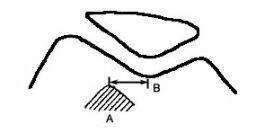

Использование аксиального снимка при 30° позволяет также рассчитать индекс Бернажо - расстояние между передней бугристостью большеберцовой кости (А) и трохлеарной выемкой (В), в норме составляющего от 10 до 15 мм (Рис. 8). Уменьшение или увеличение этого расстояния обычно свидетельствует о дисплазии мыщелков бедренной кости или надколенника, что выражается в нестабильности бедренно-надколенникового сочленения.

Рисунок 8. Индекс Бернажо. Объяснение в тексте.